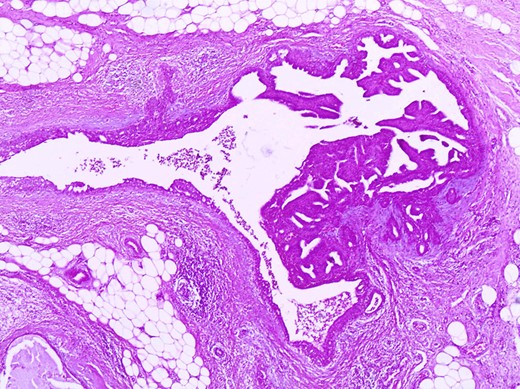

The histologic examination revealed an intraductal papilloma of 9 mm in maximum diameter with no evidence of atypia or malignancy (Figs 3,4 and 5).

The same duct with the papillary projections. The wall is fibrotic and there are also foci of usual type of epithelial hyperplasia (H+E×100).